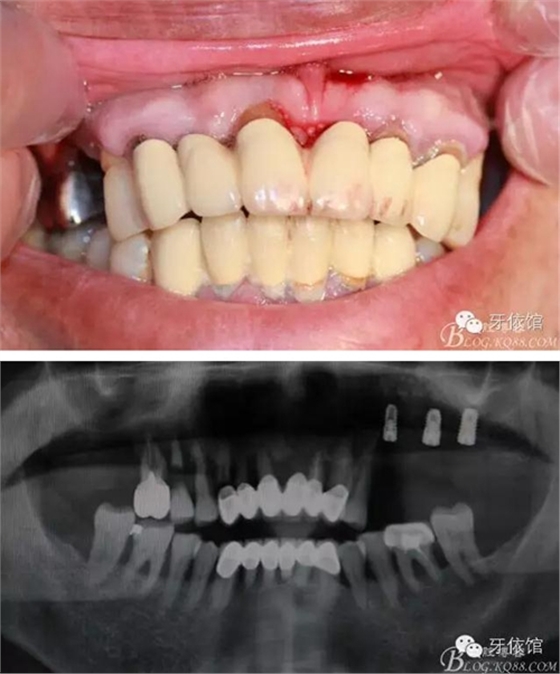

患者男,65歲,口內(nèi)多組烤瓷橋,具體時間不詳,左上5,6,7已于5個月前即可種植,OSS-TEM系統(tǒng),余留牙都已三度松動;此患者笑線高,微笑時唇緣在齦緣上4mm。

術(shù)前口內(nèi)照和X光片